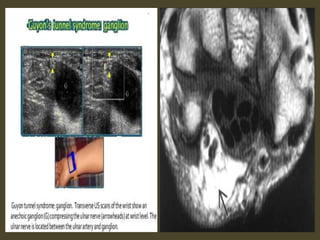

Lipoma at the Ulnar tunnel.

Ganglion cyst.